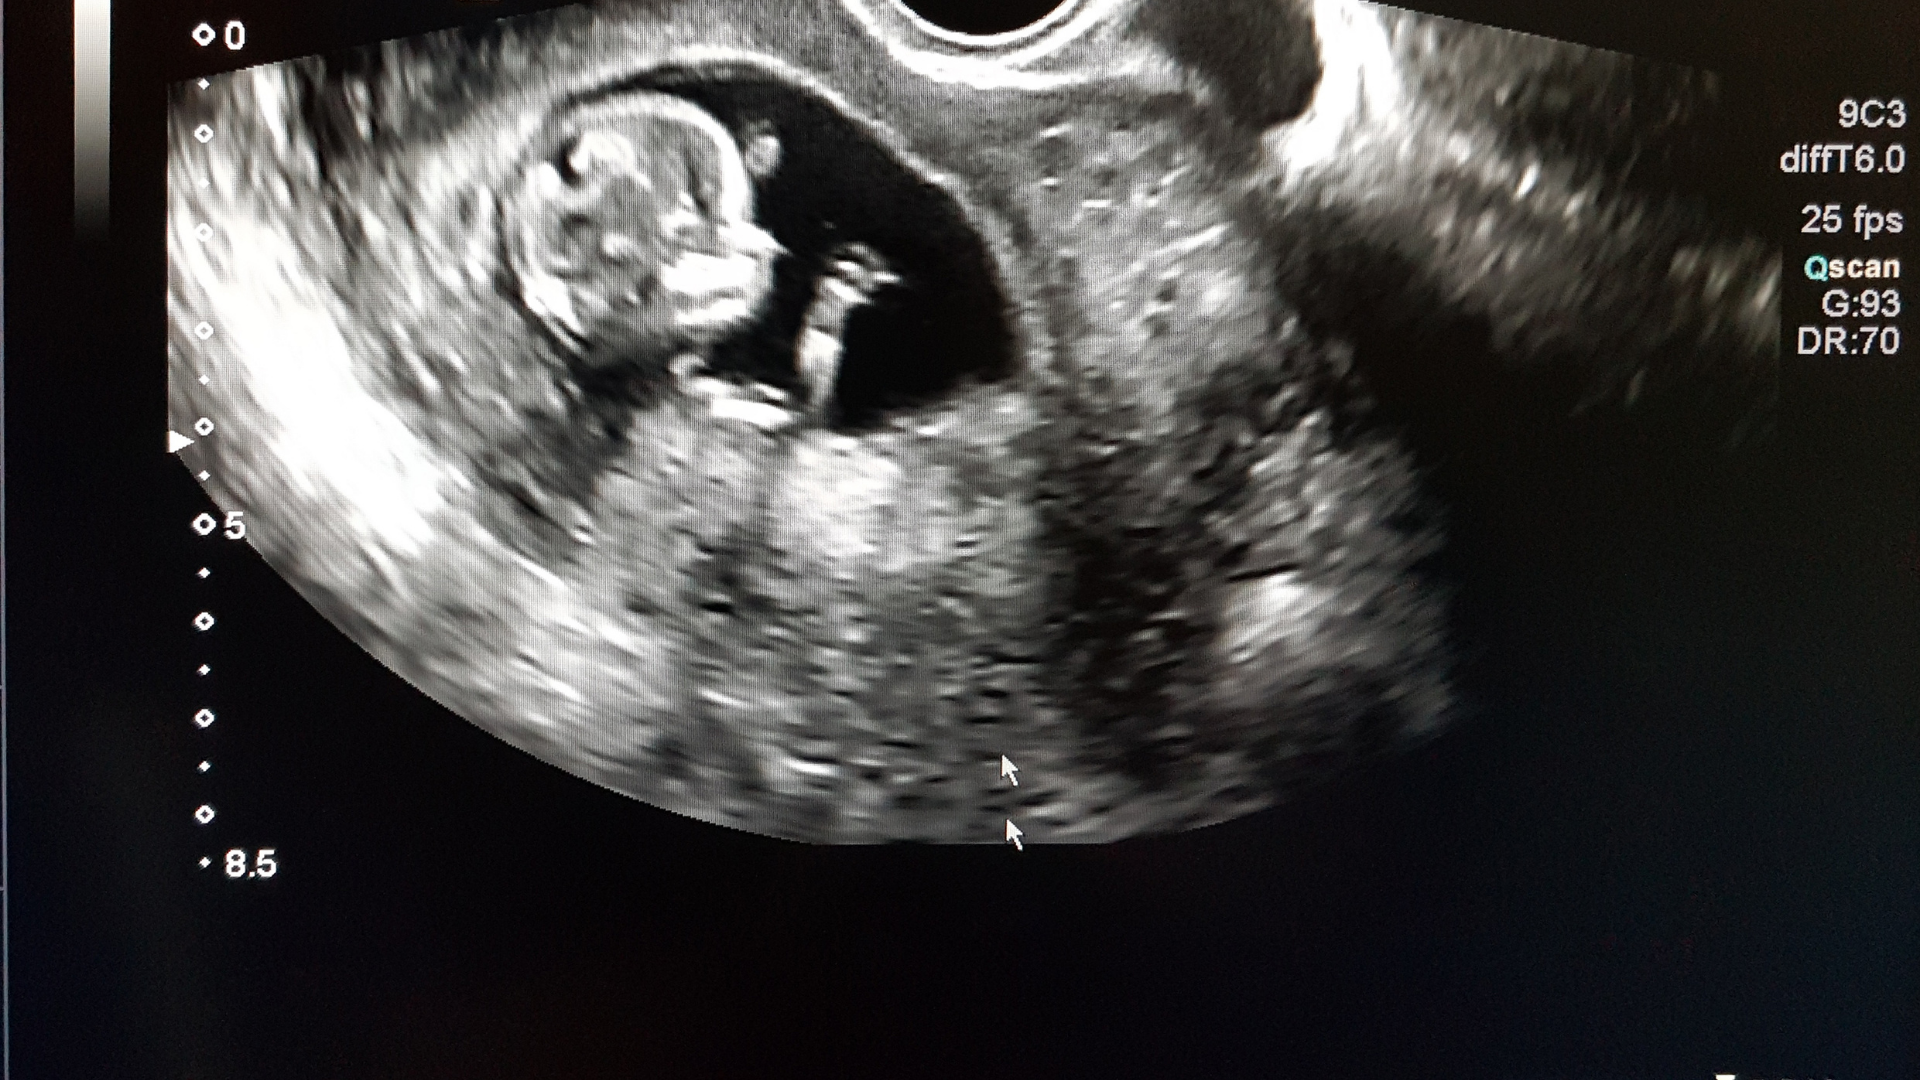

Ở thời điểm này, thai nhi thường có chiều dài khoảng vài centimet, với các bộ phận như đầu, tay và chân đã hình thành khá rõ. Tim thai hoạt động ổn định và một số cấu trúc cơ thể bắt đầu hoàn thiện.

Đây cũng là giai đoạn cơ quan sinh dục bắt đầu phát triển. Tuy nhiên, sự khác biệt giữa bé trai và bé gái vẫn chưa rõ ràng hoàn toàn trên hình ảnh siêu âm.